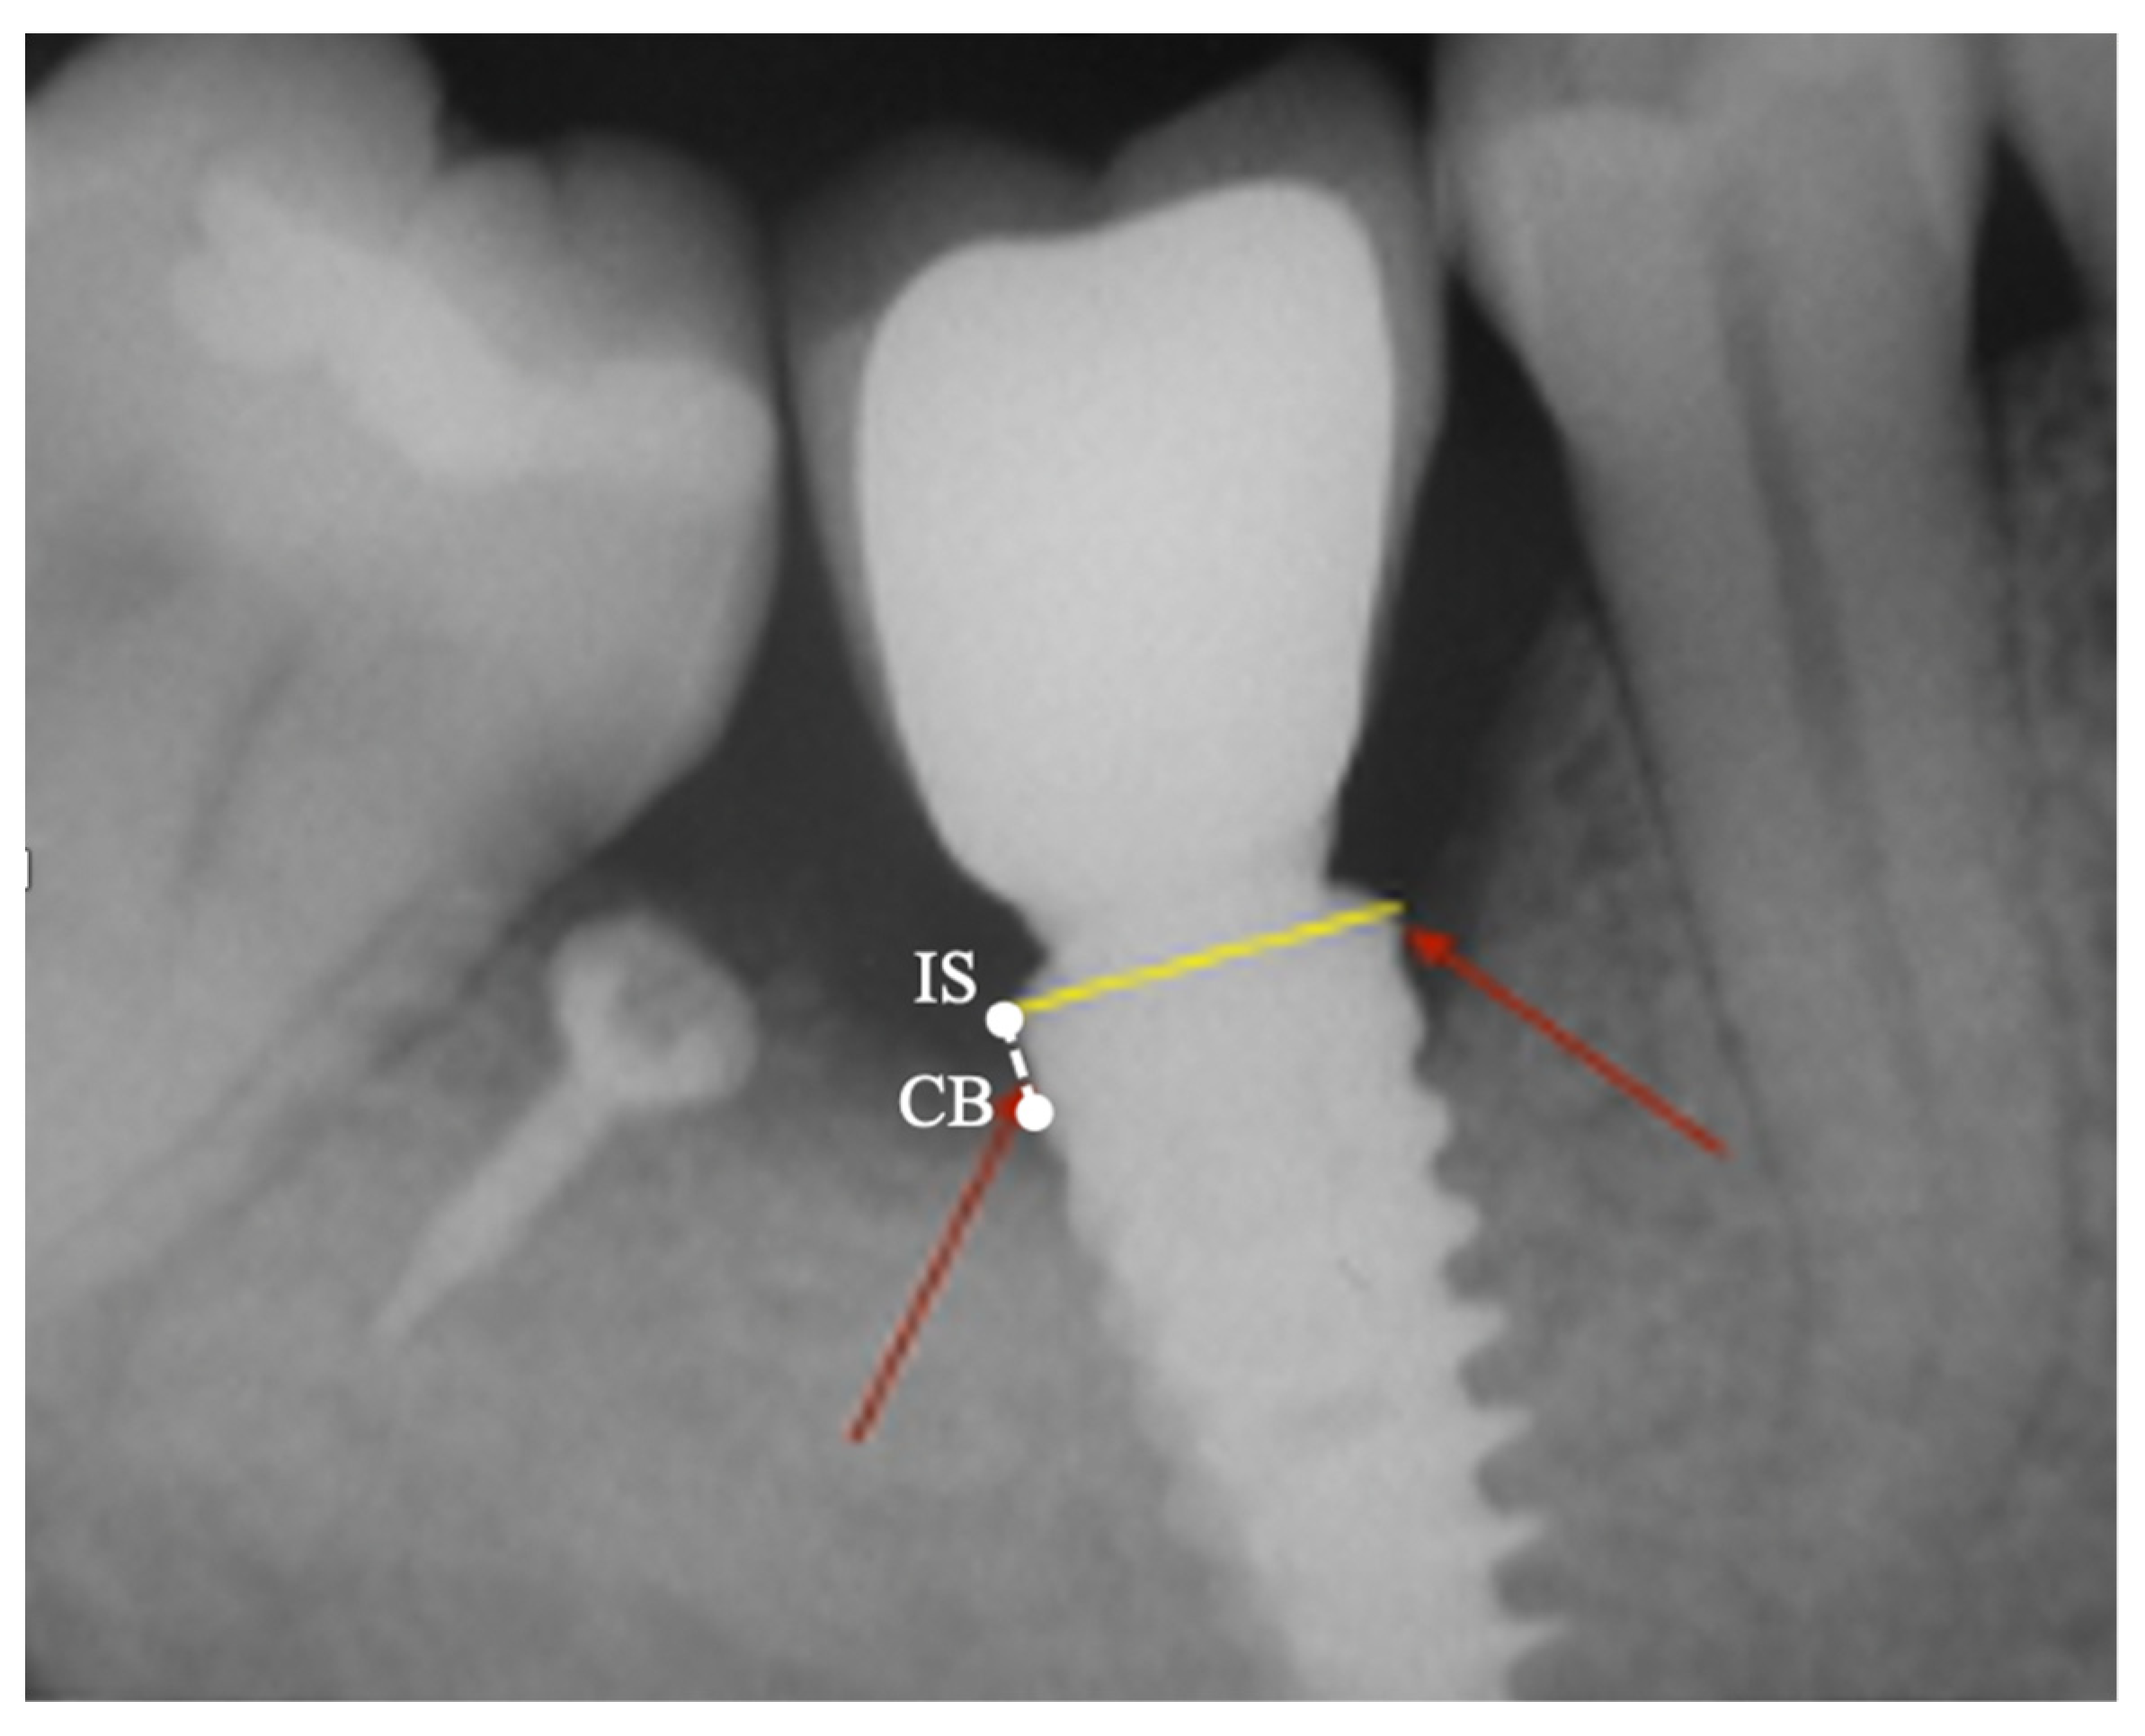

2.3. Peri-Implant Bone Levels Assessment